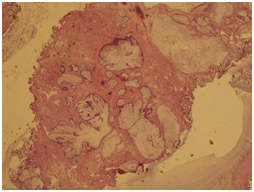

A complete blood count, liver function test, urine culture and PSA were all within normal ranges. Urine cytology revealed atypical cells. CT abdomen and pelvis with I.V contrast showed a 3.1 x 2.4 x 3 cm polypoidal mass of the trigone (Figure 1). Afterwards, the patient underwent cystoscopy which showed a solid florid mass extending from the trigone to the posterior wall of the urinary bladder, TURBT was carried out. The Histopathology slides showed cystitis cystica with cystitis glandularis (Colonic metaplasia) (Figure 2‒5).

Figure 1 A polypoidal mass and thickening of the trigone, no lymphadenopathy or metastasis could be seen.